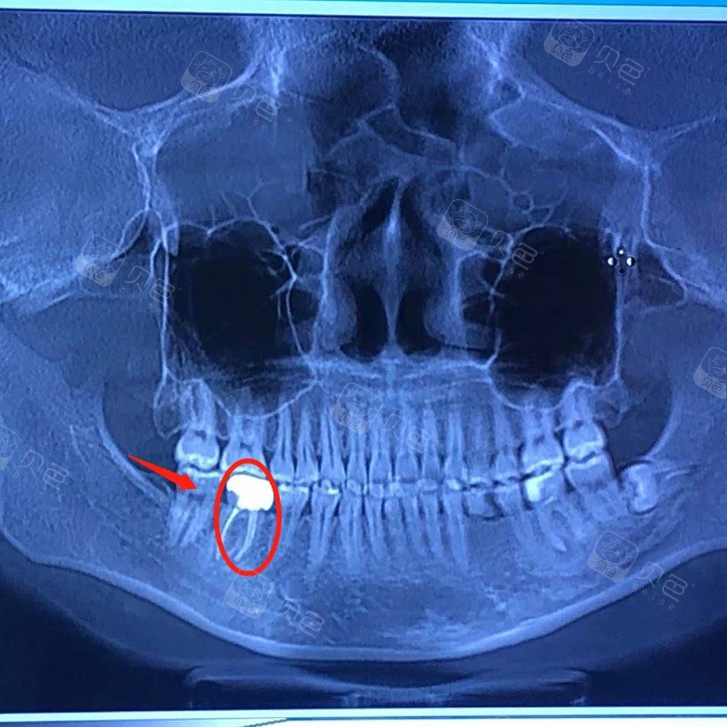

病例十三下颌第一磨牙根管治疗一例

图片尺寸258x388